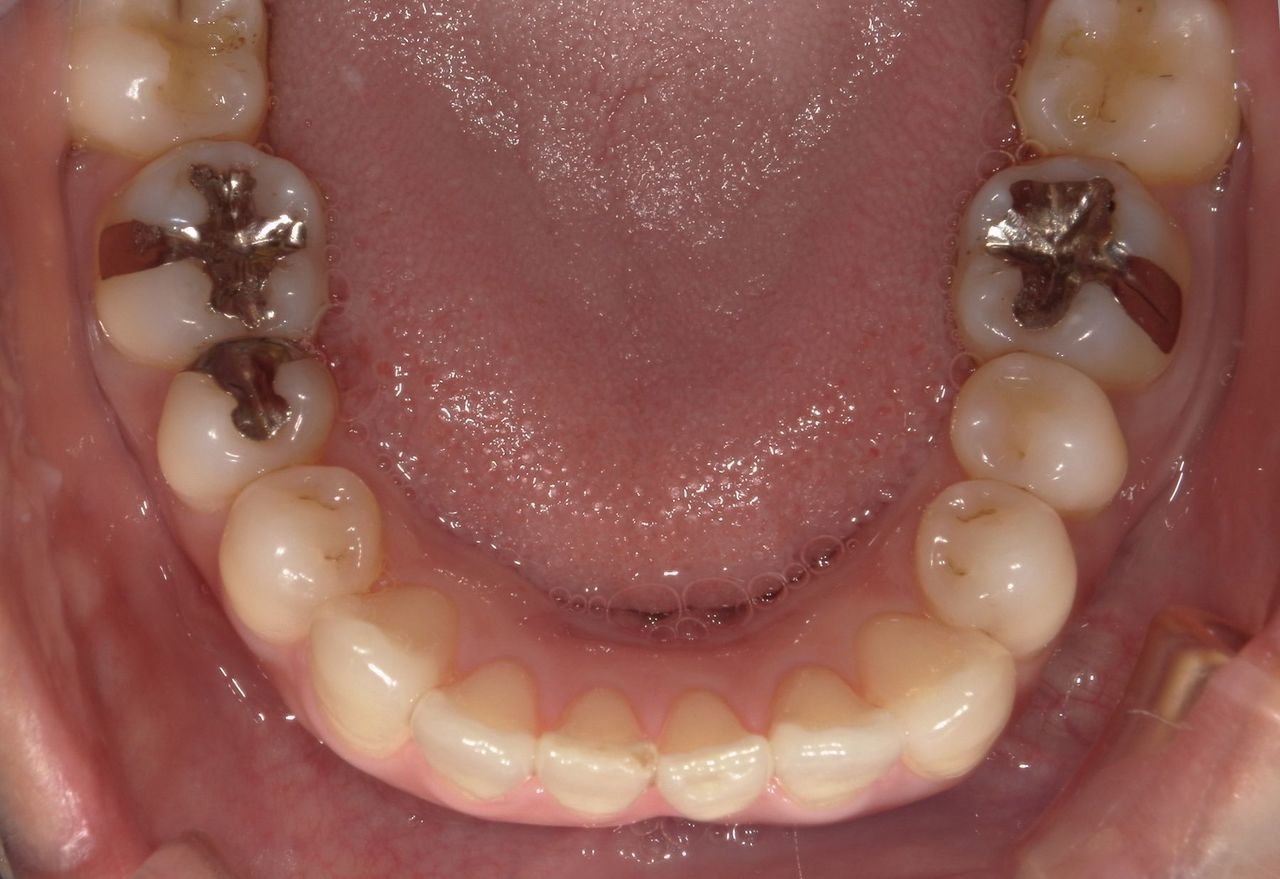

手の湿疹がなかなか治らないので皮膚科を受診したが、原因が不明で「口の中の金属が原因かも。」と言われた。

当院でパッチテストをしたところ、パラジウムとインジウムに陽性反応がみられたため金属を除去した。

左下6番目にメタルインレーが装着されていた。銀歯を除去して、保険適応の白い詰め物をした。数ヵ月後から皮膚症状の赤みが少なくなり目立たなくなった。

アレルギーの原因としては、金属以外にもハウスダストや食品なども考えられるので総合的な治療が必要なケースが多い。

左下6番目に銀歯が装着されている。

銀歯を外して、虫歯を削ってから保険適応の詰め物をした。